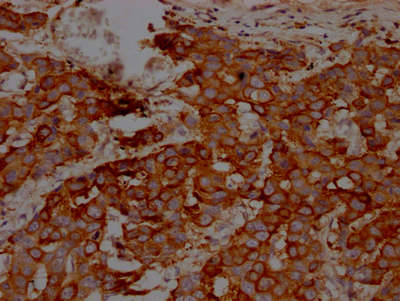

IHC image of CSB-RA256500A0HU diluted at 1:100 and staining in paraffin-embedded human breast cancer performed on a Leica BondTM system. After dewaxing and hydration, antigen retrieval was mediated by high pressure in a citrate buffer (pH 6.0). Section was blocked with 10% normal goat serum 30min at RT. Then primary antibody (1% BSA) was incubated at 4℃ overnight. The primary is detected by a Goat anti-rabbit IgG polymer labeled by HRP and visualized using 0.05% DAB.